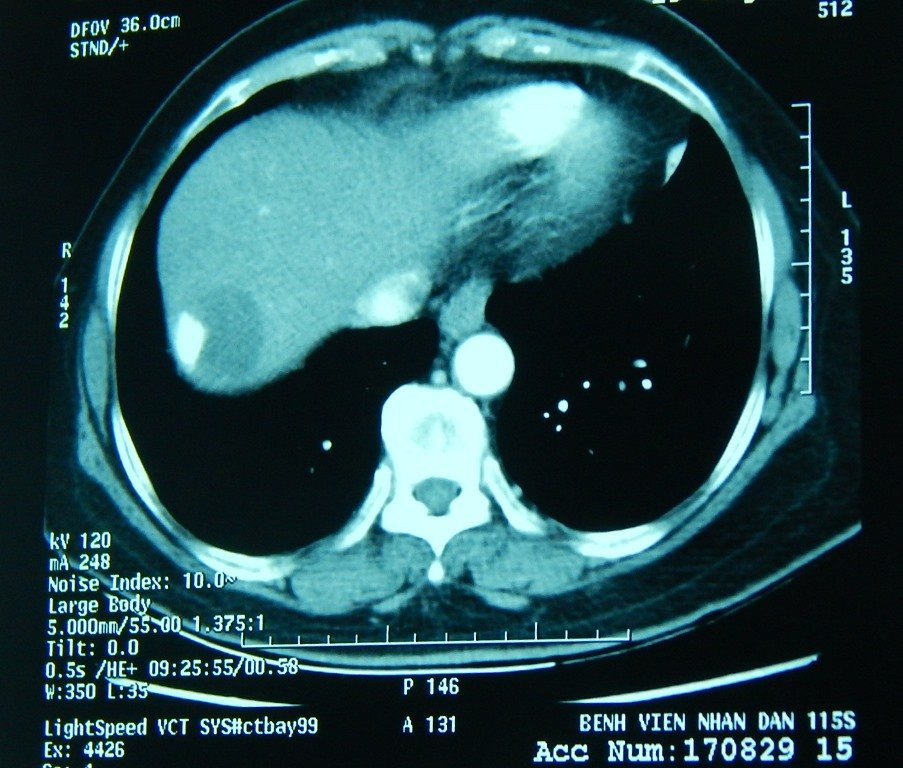

Bệnh nhân là bà Ngô Kim Th. (67 tuổi, sống tại tỉnh Tây Ninh) nhập viện tại Bệnh viện Nhân dân 115 vào ngày 28/8 với chẩn đoán bị ung thư gan. Bệnh nhân được phát hiện có một khối u khá lớn với kích thước 6x7 cm, nằm sát màng phổi.

Vị trí khối u gan của bệnh nhân Ngô Kim Th. được thể hiện qua phim X-quang